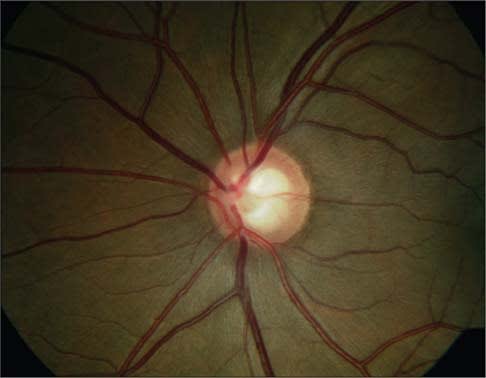

Notice the thinning of the inferior neural retinal rim in this glaucomatous optic nerve.

"Optic nerves can be large, small or average in size, but what you want to see [in a healthy optic nerve] is the rim tissue following a specific pattern of thickness," she says. "Typically, the thickest area of rim tissue should be in the inferior quadrant followed by the superior, then nasal, then temporal quadrant. Any deviation from this is an alert for glaucoma."

"I look for whether the neuroretinal rim tissue is thin at any points and whether there is any change in the banking of the blood vessels there," she says.

Specifically, she looks to see whether the blood vessels are changing direction and bending in a more horizontal fashion around the neuroretinal rim and cup edge of the optic nerve.

Dr. Muckley adds that she uses the inferior, superior, nasal and temporal (ISNT) rule in evaluating the margins of the neuroretinal rim tissue for deterioration.